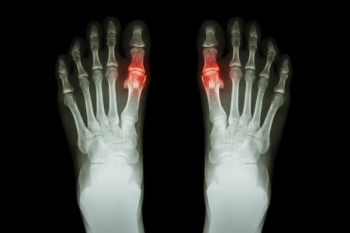

Gout is a form of arthritis that is caused by a buildup of uric acid crystals in the joints. This considered to be one of the most frequently recorded medical illnesses throughout history. Gout occurrences in the US have risen within the past twenty years and the condition now affects 8.3 million people which is 4% of all Americans. Researchers have found that gout affects men more than women and African-American men more than white men.

Symptoms of gout are warmth, swelling, discoloration, and tenderness in the affected joint area. The small joint on the big toe is the most common place for a gout attack to occur.

People who are obese, gain weight excessively, drink alcohol heavily, have high blood pressure, or have abnormal kidney function are more likely to develop gout. Furthermore, certain drugs and diseases are likely to increase levels of uric acid in the joints which eventually leads to gout. You are also more likely to develop gout if you eat a lot of meat and fish.

Many who experience gout attacks will experience repeated attacks over the years. Some people who have gout symptoms, may never have them again, but others may experience them several times a year. If you have gout symptoms throughout the year, you may have recurrent gout. Those who have gout should also be careful about their urate crystals collecting in their urinary tract, because this may lead to kidney stones.

Diagnosis for gout is done by checking the level of uric acid in the joints and blood. Your podiatrist may also prescribe medicine to reduce uric acid buildup in the blood, which will help prevent any gout attacks.

To treat gout, your podiatrist may also prescribe you Anti-inflammatory medication (NSAIDs) which will relieve the pain and swelling of a gout episode and it can also shorten a gout attack. Maintaining a healthy diet is also a proven method to prevent gout attacks.

Risk Factors and Symptoms of Gout

Gout is a form of arthritis caused by the buildup of uric acid crystals in the joints. This buildup occurs when the body produces too much uric acid or cannot effectively eliminate it. Risk factors for developing gout include a diet high in red meat and seafood, excessive alcohol consumption, and obesity. Certain medical conditions such as hypertension and diabetes also increase the likelihood of developing gout. Symptoms of gout often appear suddenly and include intense joint pain, redness, and swelling, typically in the big toe. The affected joint may feel warm and extremely tender to the touch. Gout attacks can be recurrent, leading to chronic pain and joint damage if left untreated. The pain from gout can be debilitating. If you have developed this condition, it is suggested that you consult a podiatrist who can offer you relief and prevention methods.